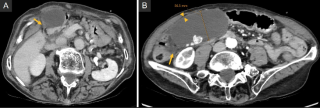

An 82-year-old male presented to the emergency department with acute-onset lower abdominal pain and one episode of vomiting. His medical history was unremarkable, with no prior abdominal surgery. Laboratory tests revealed elevated lactate levels, while all other parameters were within normal limits. Abdominal computed tomography demonstrated a mechanical ileus with suspicion of an internal hernia.

Emergency diagnostic laparoscopy revealed partial herniation and incarceration of the small bowel through a paracolic defect. The procedure was converted to a mini-laparotomy, with mobilization of the ileocecal region, followed by segmental ileal resection approximately 1 meter proximal to the ileocecal junction, due to questionable bowel viability and a tight strangulation ring. The patient received intravenous antibiotic therapy, and oral intake was gradually reintroduced without complications. After satisfactory wound healing and decreasing inflammatory markers, secondary closure of the laparotomy wound was performed, followed by a rapid and uneventful postoperative recovery.